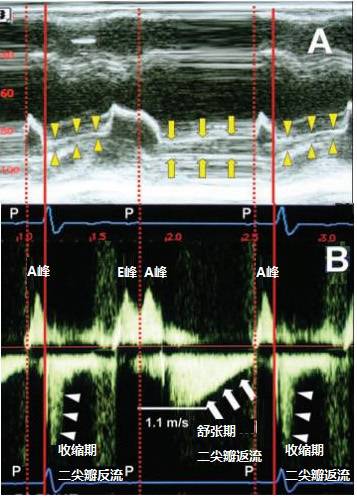

图3所展示的一位78岁女性,存在2:1房室阻滞时的心脏彩超可解释这一问题。

图3A可见:黄色三角形显示二尖瓣轻度收缩期关闭不全,第一个P波出现后,启动心房的兴奋收缩偶联,即心房发挥辅助泵功能,图中可见跨二尖瓣血流,即A峰(图3B所示,心房收缩期,即心室的减慢充盈期)。

经过P-R间期延迟后,P波下传心室,激动心室,形成QRS波,启动心室的兴奋收缩偶联,心室收缩,出现收缩期二尖瓣反流(图3B白色三角所示)。随后,心室进入快速充盈期,左心房血液顺压力梯度进入左心室,形成E峰(图3B所示),后出现第二个P波,同样启动心房的兴奋收缩偶联,心房收缩,心室进入减慢充盈期,跨二尖瓣血流形成A峰。但由于第二个P波未下传,故并无随后的心室收缩,导致心室的舒张期过度延长,二尖瓣不是从开放状态走向闭合,而是继续开放,左心室腔压力升高的速度超过左心房压上升的速度。

图3B中,左心房排空后(即A峰后),左心室和左心房之间的舒张压梯度很快升高,最高达4.8mmHg,由于本身存在二尖瓣关闭轻度不全,因此出现了舒张期的二尖瓣反流(Diastolic Mitral Regurgitation,DMR)(图3B,白色箭头),在左心房开始充盈后这个压力梯度逐渐减低,直至下一次P波出现、心房收缩期到来,心房压超过心室压,舒张期反流才停止。

图3:2:1房室阻滞二尖瓣舒张期反流。垂直实线描绘心室收缩的开始,以QRS波群开始为特征;垂直虚线描绘心房收缩的开始;心电图上相应的P波在图中标注。A:M型在胸骨旁左心室长轴切面二尖瓣瓣尖;B:跨二尖瓣血流的连续波(CW)多普勒心尖四腔切面观